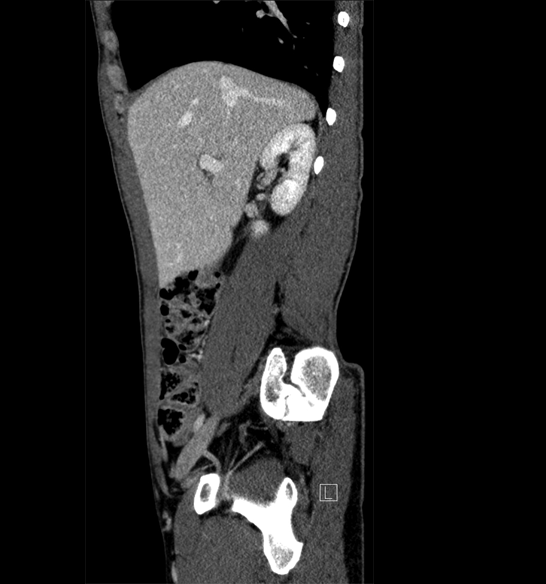

Body

Covers abdominal CT anatomy.